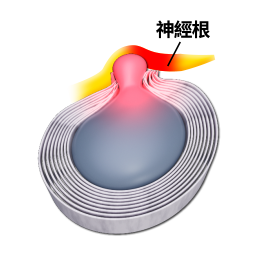

主要頸源性頭暈、頭痛的成因: (1)上頸椎神經受壓:

因為頸椎分為上頸椎和下頸椎,頸椎C3節為分介線,C3以上椎節為上頸椎節,C3以下椎節為下頸椎節。凡是上頸椎神經受壓,例如:椎間盤突出、椎孔狹窄、椎體移位或下陷,都會有機會導致前額痛、後枕痛、眼窩痛、上頸椎痛。

目前,採用強力後枕牽引器(N05b) 拉直頸椎,減少病變對神經的受壓,減少刺激交感神經,同時可拉直血管,使血液流通暢順。此方法可從根源解決頸源性頭暈、頭痛、眼花等問題,非常有效。

先讓病人頭部保持後仰姿勢,並以後枕作為支點,再扭動兩側升降桿的扭制,產生巨大後枕牽引力(最高可達到20Kg)有效拉直上頸部,減少刺激交感神經,減少頸椎神經受壓和暢順頸部血管。

椎間盤突出

椎間盤回縮